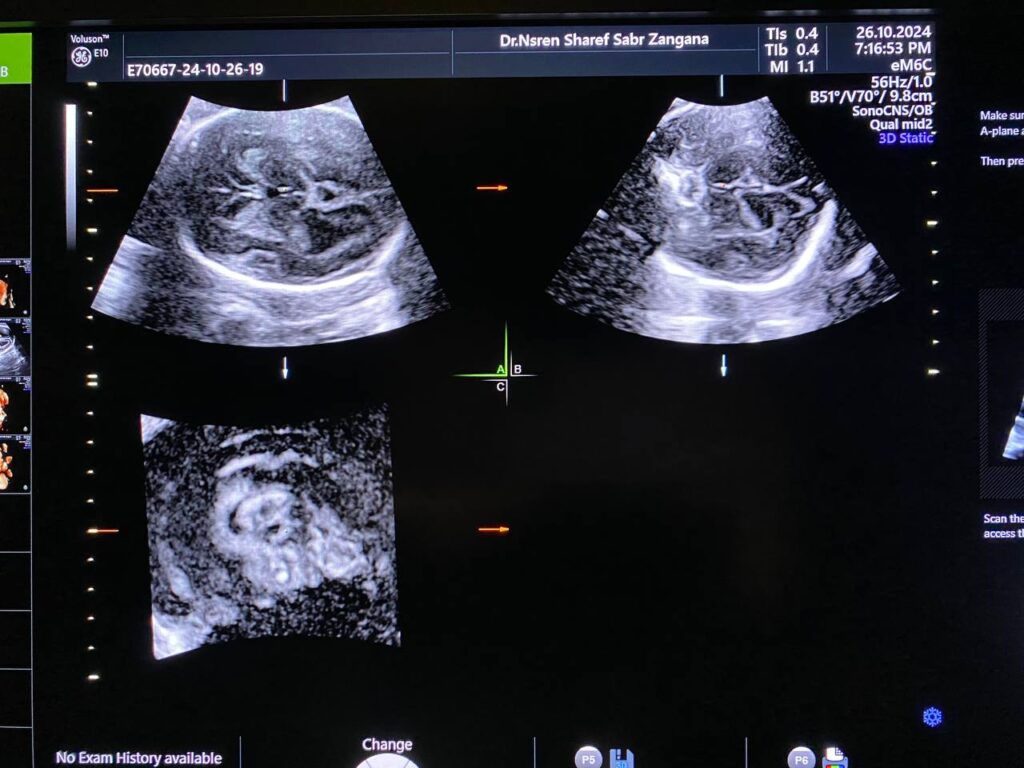

Brain: mild to moderate dilated lateral ventricles 16mm, with remaining cerebral mental about 13mm, dilated third ventricle, normal fourth ventricle, Picture mostly of Hydrocephaly due to aqueduct of Sylvius stenosis